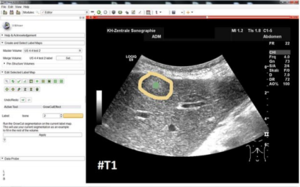

- 1.70 Interactive Outlining of Pancreatic Cancer Liver Metastases in Ultrasound Images

- 1.71 The Evolution of Cost-efficiency in Neural Networks during Recovery from Traumatic Brain Injury